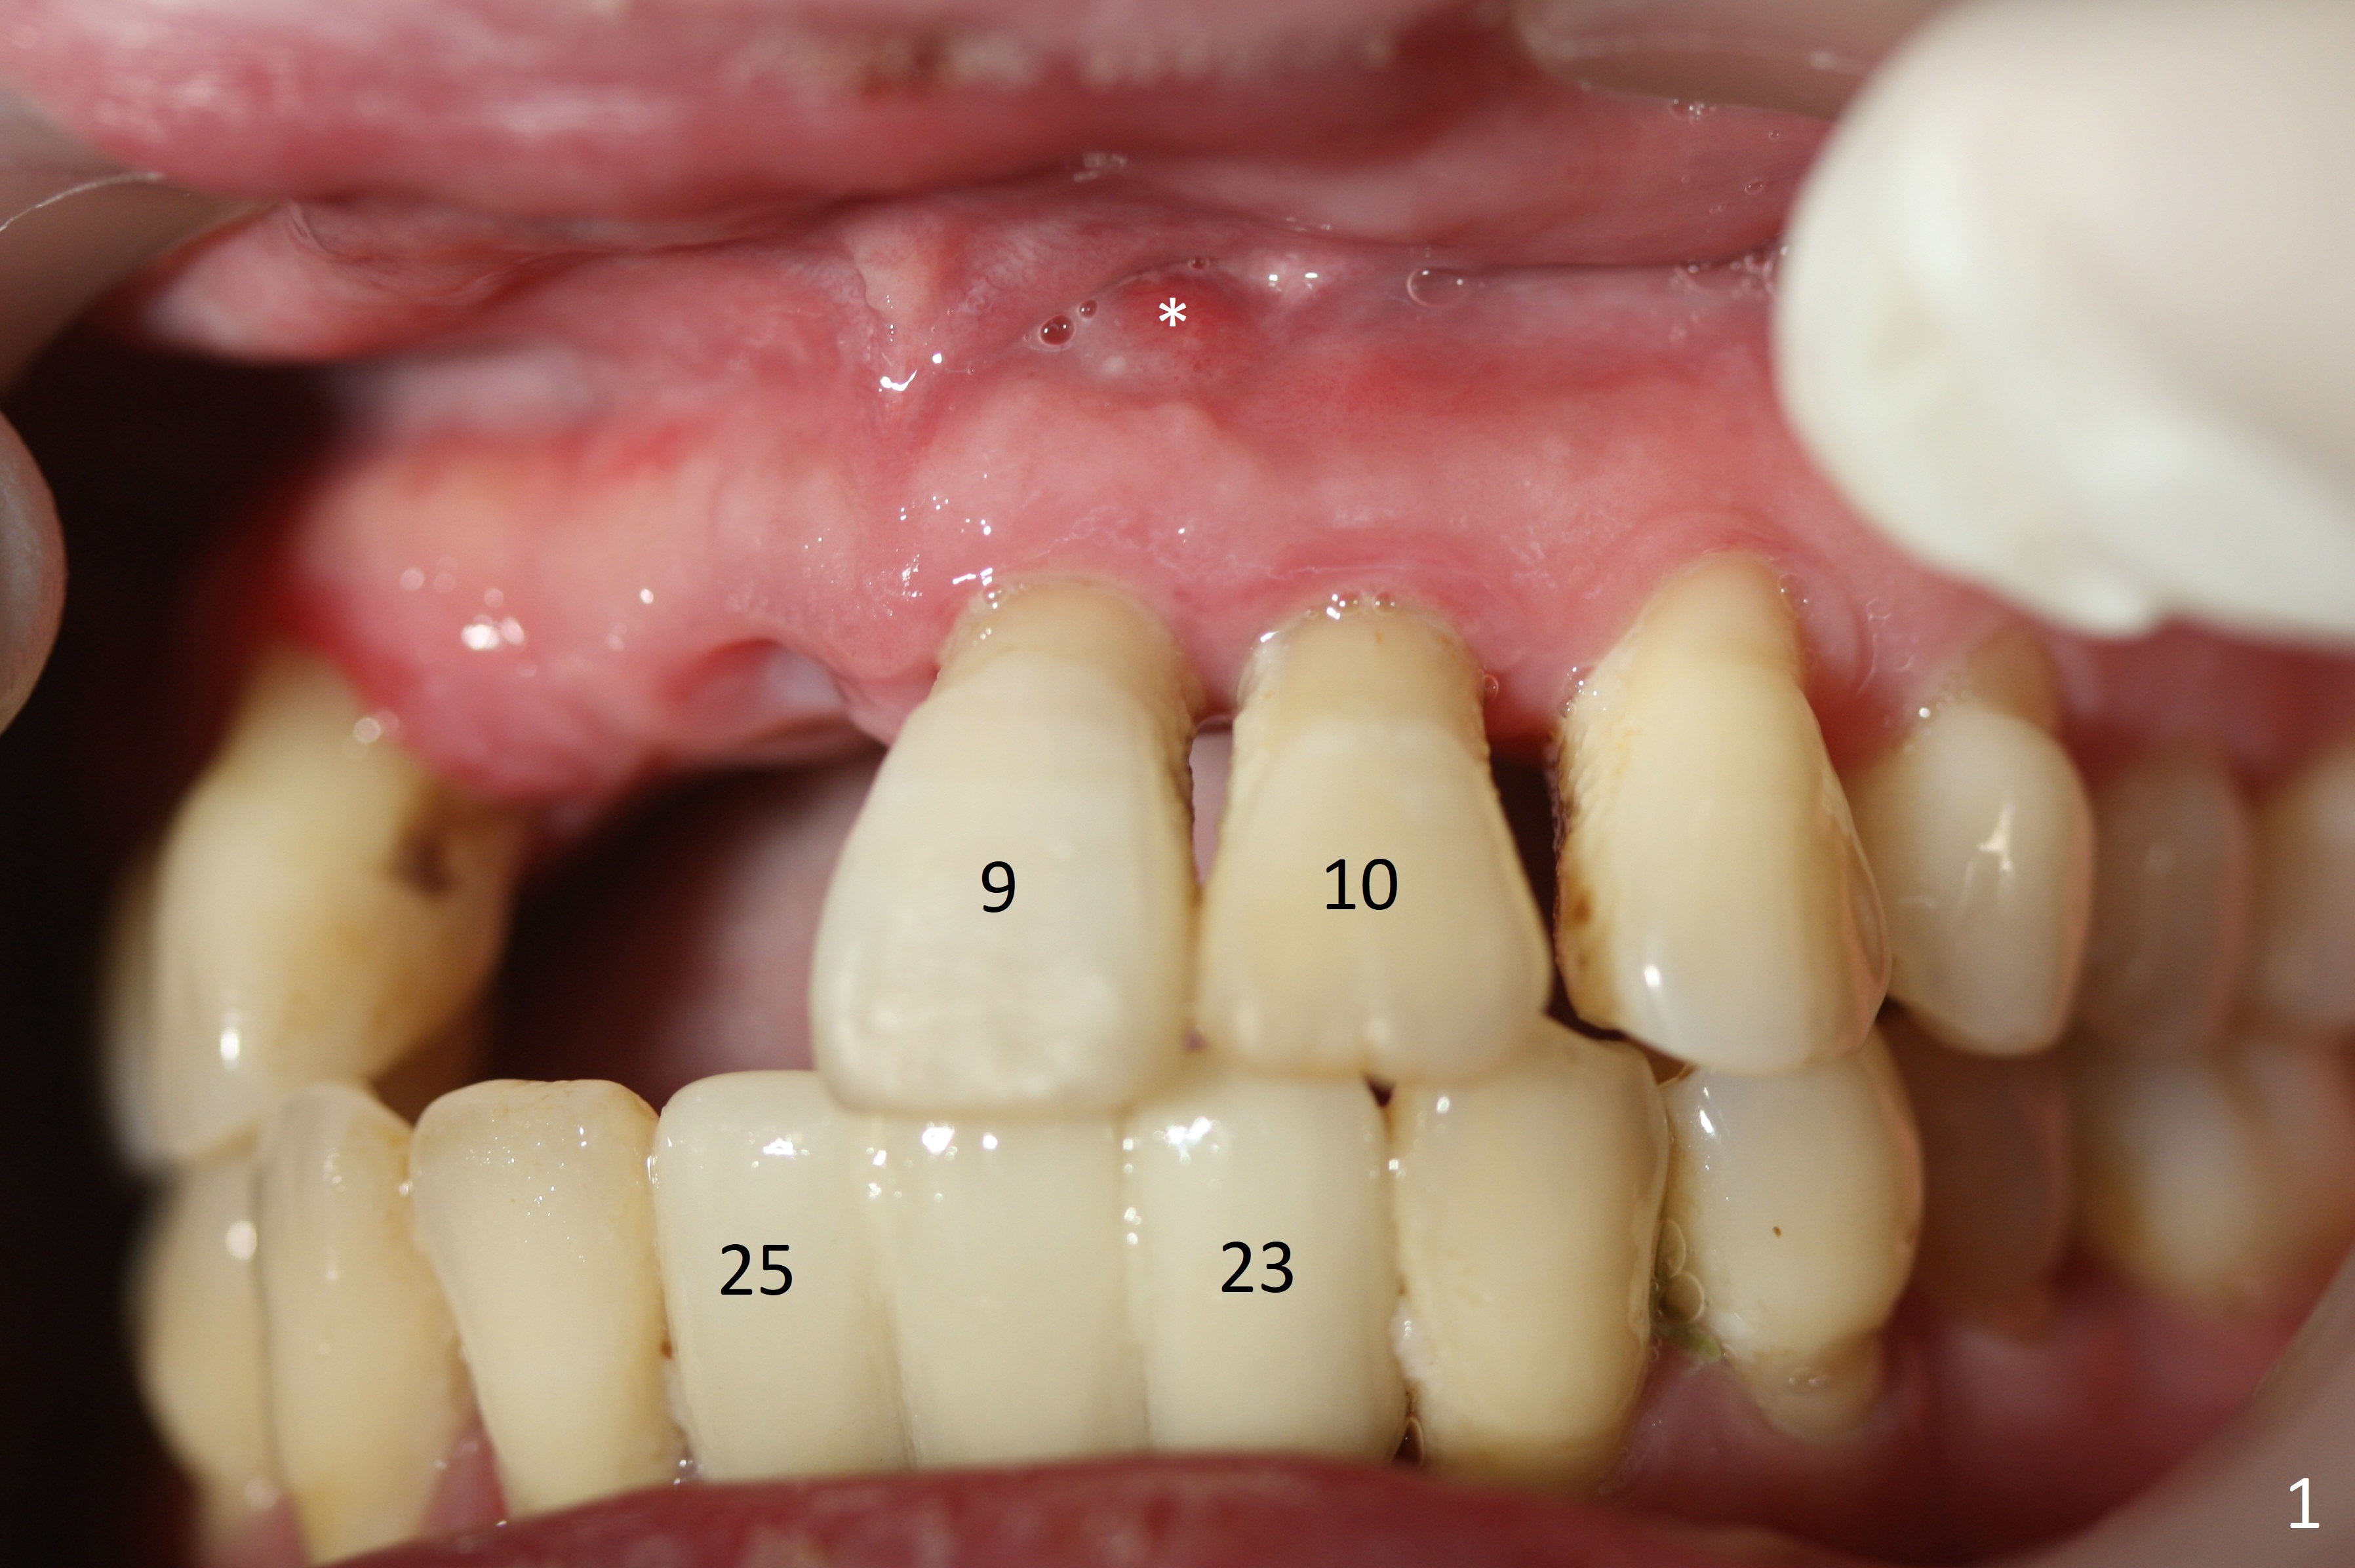

A 41-year-old woman returns to clinic with missing upper right incisors and mobile left ones (#9 fistula (Fig.1 *) 2 years post cementation of 23-25 implant FPD (Fig.2-3). The Incisive Canal is large (Fig.2,3 *). Place all of the 4 implants distally (2.5 or 3x10 or 12 mm (at 8,9), x12 or 14 mm (7,10)) and as deep as possible. The cuff is most likely 4 mm.